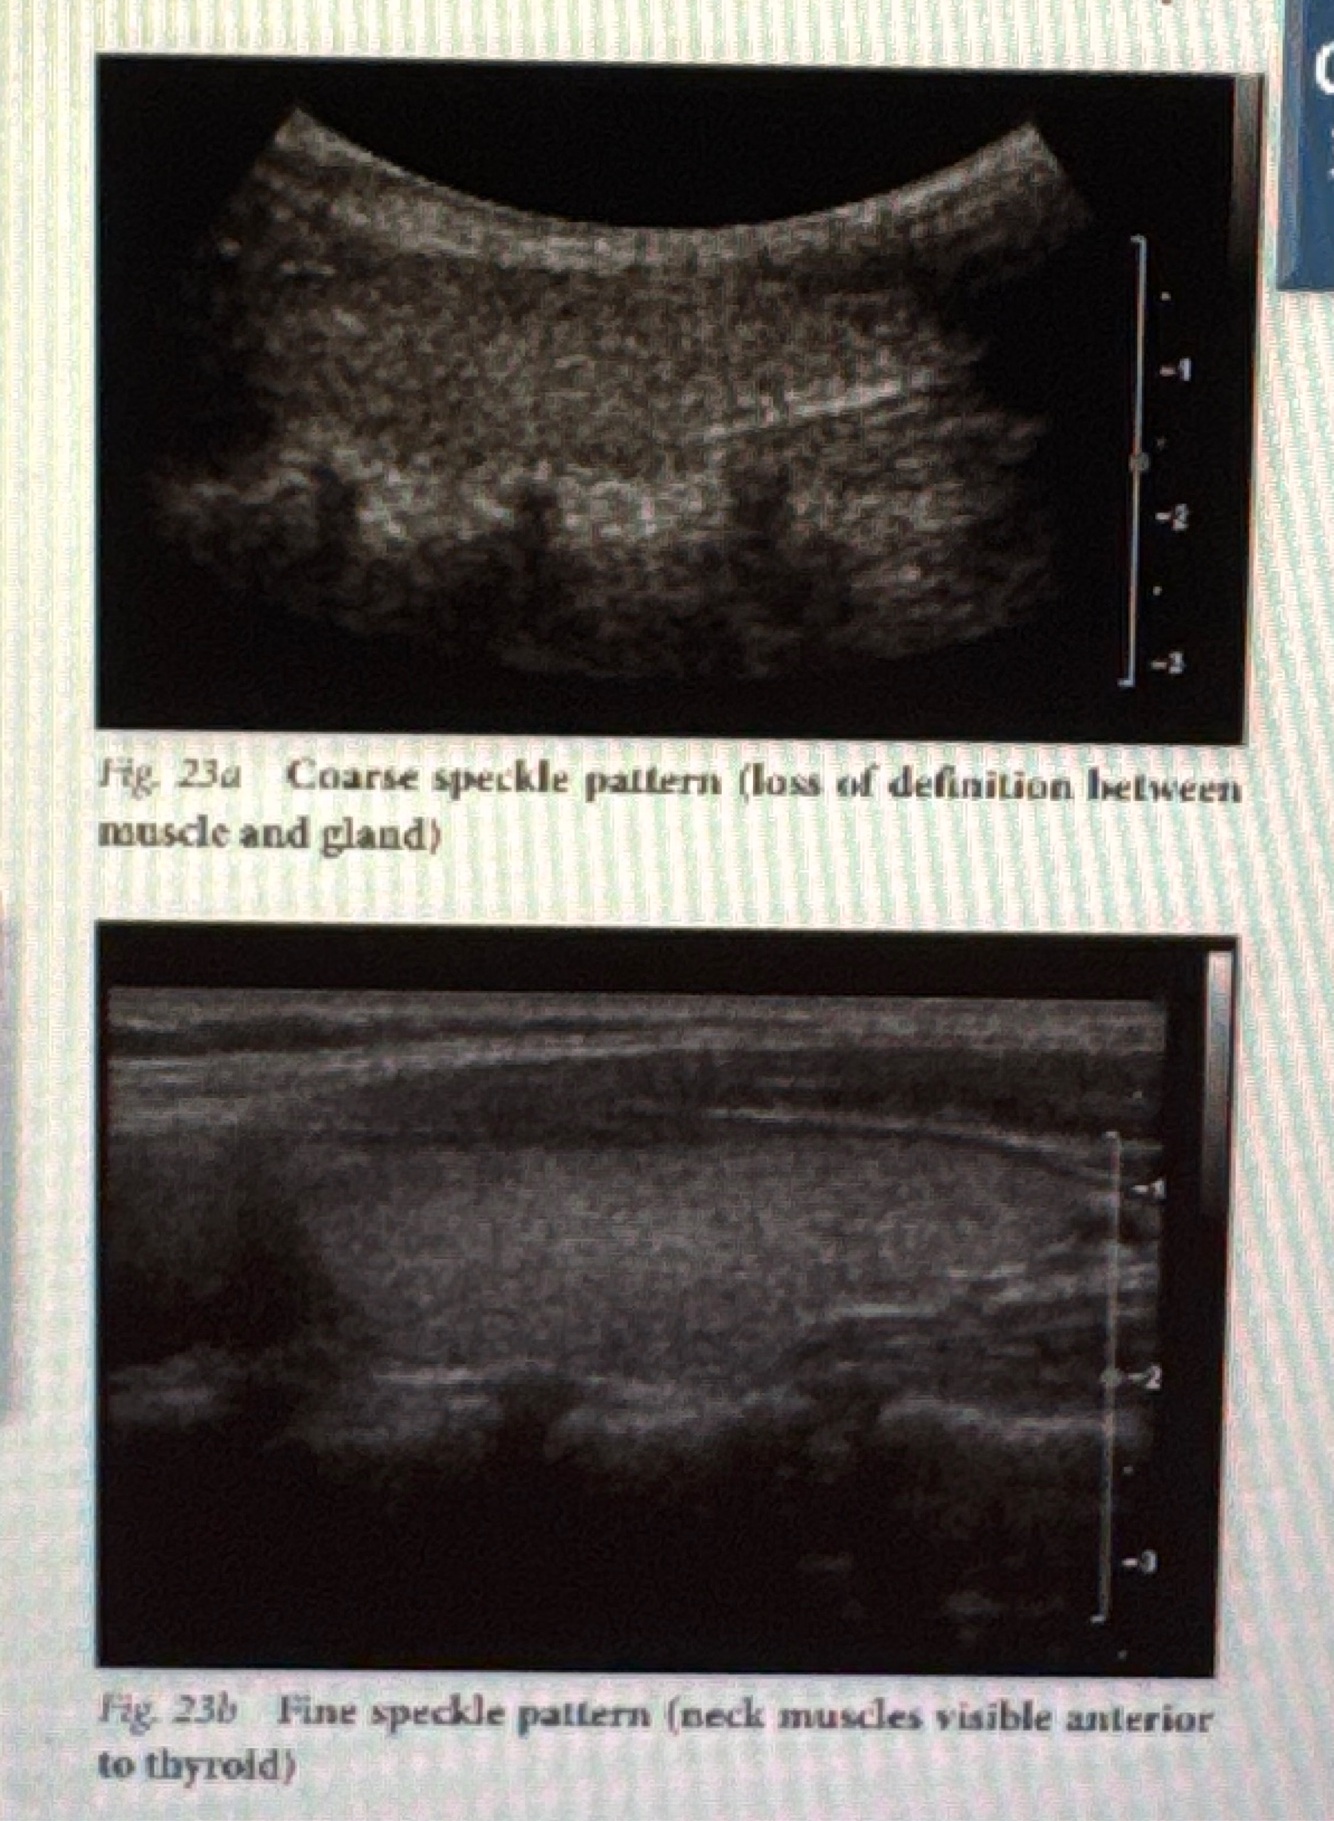

What are two types of speckle patterns and their characteristics

• coarse speckle patterns: rough looking texture (larger black spaces)

• fine speckle pattern: smooth looking texture (smaller black spaces)